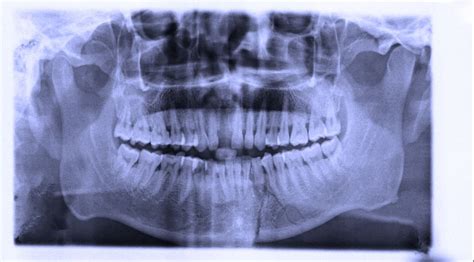

Are you wondering if dentists can transfer x-rays? You're not alone. Many people have questions about this topic, and in this article, we'll provide all the answers you need. Whether you're a dental professional or a patient, understanding the process of transferring x-rays is essential for effective diagnosis and treatment. So, let's dive in and explore the world of x-ray transfer in the dental field.

Yes, dentists can transfer x-rays. With the advancements in technology, transferring x-rays has become much easier and efficient. Dentists can now digitally send x-ray images to other dental practices or specialists through secure online platforms. This allows for quick and seamless communication between dental professionals, leading to better collaboration and improved patient care.

X-ray transfer in dentistry involves the digital transmission of radiographic images between dental professionals. Instead of physically mailing or hand-delivering x-ray films, dentists can now send high-quality digital images electronically. This process not only saves time and resources but also allows for easier collaboration and consultation between dental practices.

When a dentist needs to transfer x-rays, they can use a secure online platform specifically designed for dental imaging. These platforms typically require the dentist to upload the x-ray images, provide relevant patient information, and select the recipient. The images are then encrypted and securely transmitted to the recipient, who can access them through the platform's interface.

With digital x-ray transfer, dentists can easily share images with specialists for consultations or refer patients to other practices while maintaining the privacy and security of patient information. This technology has revolutionized the way dental professionals collaborate and provide comprehensive care to their patients.